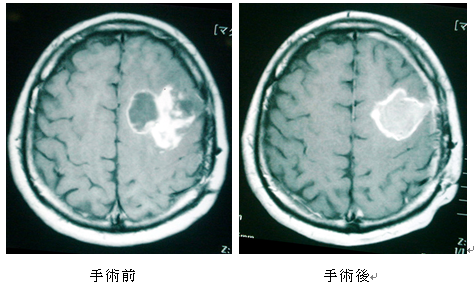

• ガドリニウムを使用した MRI: MRI スキャンにより、医師は人の脳の正確な画像を作成できます。ガドリニウムは、脳腫瘍と典型的な組織との間にコントラストを与える注射可能な物質です。

• 手術:場合によっては、神経膠腫を除去する手術がオプションとなる場合があります。医師は手術前に化学療法や放射線療法を推奨する場合もあります。